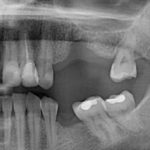

Заметить проблему можно намного раньше, чем она даст о себе знать. Так, во время гигиены ротовой полости можно увидеть, что около некоторых зубов ткани начали немного провисать. Или наоборот, может обнажиться шейка резца. Ясно одно: с мягкими поверхностями что-то происходит. Одновременно человек ощущает дискомфорт, внезапно возникающий после приема холодной или горячей пищи. Уже сейчас важно быстрее обратиться к врачу, чтобы узнать, почему проваливается десна, и что с этим делать. Доктор может найти причину в следующем:

- пародонтоз в запущенной стадии.

Если провалилась десна, врач всегда сначала удаляет зубной камень, когда это необходимо. Дело в том, что даже при регулярной гигиене остаются зоны, которые человек очищает ненадлежащим образом. Со временем там скапливается грязь, налет. Последний накапливает частички пищи, бактерии. Со временем он твердеет, образуя зубной камень, давящий на корни зубов. Образуются микропорезы, через которые попадает инфекция. Поэтому мягкие области могут воспалиться.